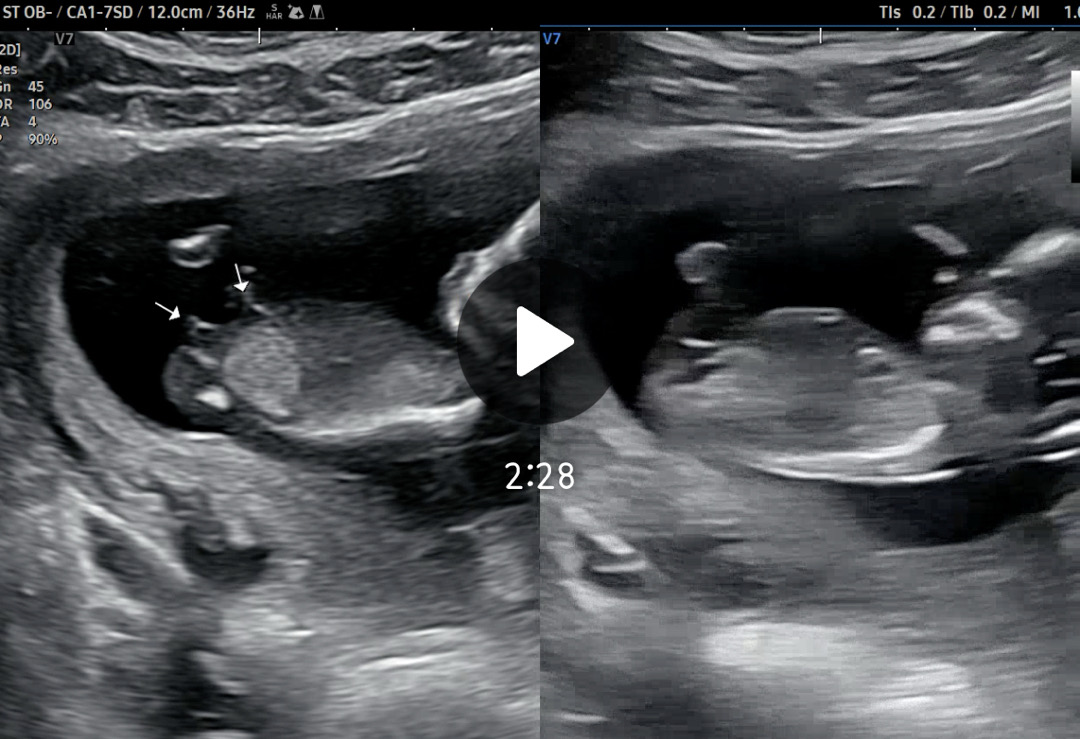

각도법 봐주세요🩷영상캡쳐본이에요

뭘까유..